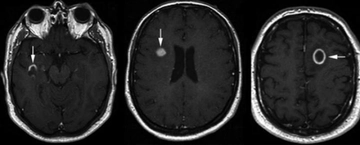

Böbrekte kistik lezyon, genellikle böbrek dokusunda sıvı dolu kesecikler (kistler) oluşturan, benign (iyi huylu) ya da malign (kötü huylu) olabilen yapılar olarak tanımlanabilir. Bu lezyonlar, böbreklerin normal işlevlerini etkileyebilir ve bazı durumlarda belirti vermeden uzun süre varlık gösterebilirler. Kistik lezyonlar, genellikle görüntüleme yöntemleriyle (ultrason, bilgisayarlı tomografi, manyetik rezonans görüntüleme) tespit edilir. Kistik Lezyonların TürleriBöbreklerdeki kistik lezyonlar, birkaç farklı türde sınıflandırılabilir:

Tanı ve Teşhis YöntemleriKistik lezyonların tanısı, çeşitli görüntüleme yöntemleri ile konulmaktadır: